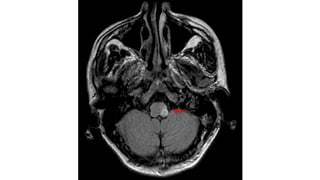

• #26 MRI of a patient with an acute cerebellar hemorrhage less than 24 hours after presentation.

Cerebellar Hemorrhage • Neurosurgicalemergency • Suspected in any patient with sudden onset headache, vertigo, vomiting and ataxia • May have gaze preference • Motor-sensory exam usually normal • Gait disturbance often not recognized because patient appears too ill to move 24

Patients who areat risk for deterioration • Admission systolic blood pressure greater than 200 mm Hg • Pinpoint pupils and abnormal corneal and oculocephalic reflexes • Hemorrhage extending into the cerebellar vermis • Hematoma diameter greater than 30 mm • Brainstem distortion • Intraventricular hemorrhage • Acute hydrocephalus